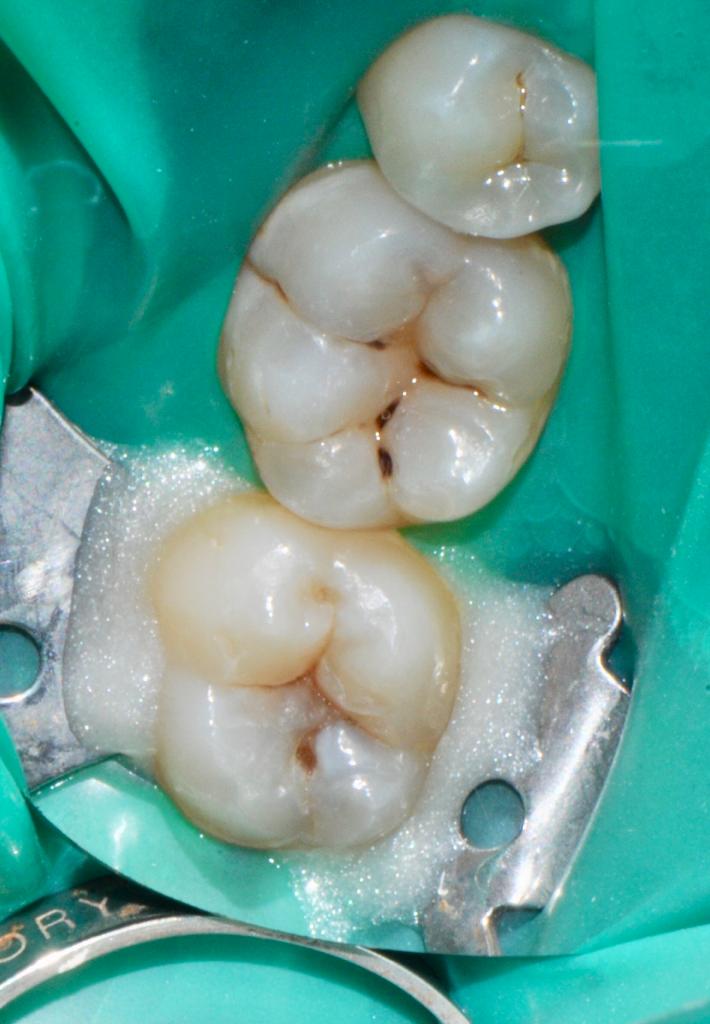

Alcuni casi clinici